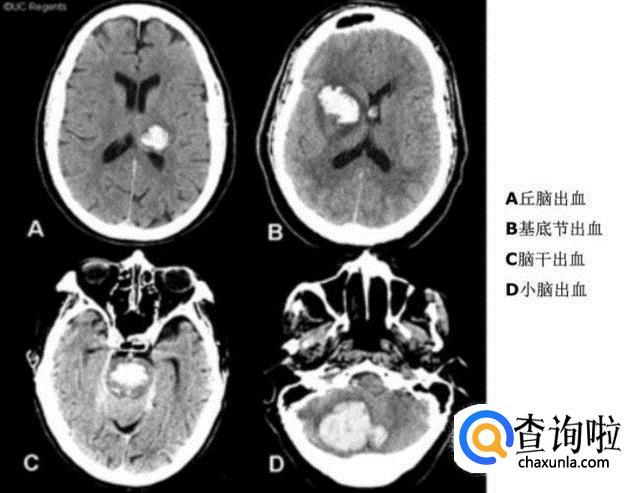

脑出血

• A皮质动脉的穿通支-------脑叶出血

• B豆纹动脉---------------壳核出血

• C丘脑穿通动脉-----------丘脑出血

• D基底动脉脑桥支---------脑桥出血

• E小脑上或小脑前下动脉---小脑出血